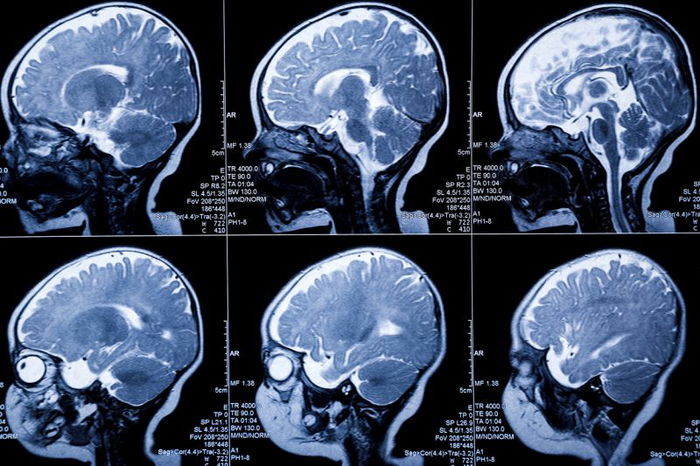

The university suggests that some environmental factors can negatively affect a child’s brain function. Along with this, they are currently preparing an infant MRI scan as part of ongoing research.

While the infants sleep, the researchers perform MRI scans on them. The study considers how the mums faced social disadvantages such as poverty. According to the findings, these newborns developed smaller brains compared to babies whose mums have higher household incomes.

The experts conducted brain scans only a few days to weeks after birth. Afterwards, the results showed minor folding of brains among infants born to mums living in poverty.

Concerning this, fewer and shallower folds signify brain immaturity. It is because a healthy human brain folds as it grows and develops. It provides the cerebral cortex with a more extensive functional surface area.